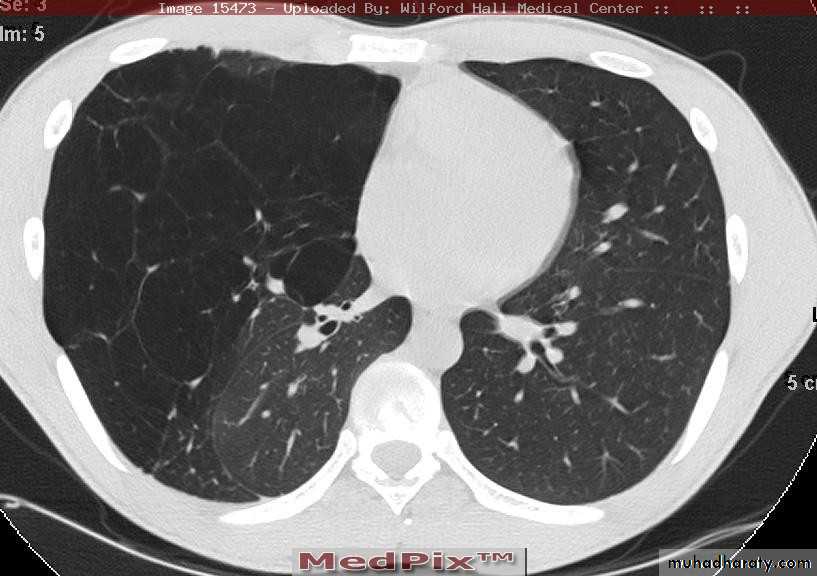

CT scan

BronchoscopyPneumothorax

Emphysema

CXR: